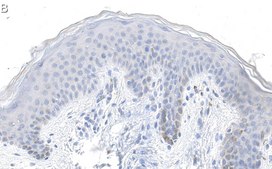

Immunohistochemistry (Paraffin) Analysis: A 1:100 dilution from a representative lot detected Laminin-5 gamma2 in human skin tissue sections.